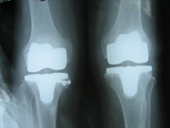

Arthriis of both hips pre op Arthriis of both hips post op Arthritis knee valgus deformity pre op Arthritis knee valgus deformity post op

Arthritis both knees varus deformity pre op Post op Total Knee Replacement Post op Total Knee Replacement